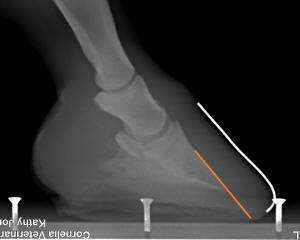

Figure 1

In a healthy hoof

with perfect lamellar connection [Figure 1] setting the correct

breakover point is easy. If you were to project the line of the

dorsal aspect of P3 to the ground (orange line) around the

perimeter of P3, you are simply outlining the sole. In front

feet, measuring from the sole, allow for 1/8” (3mm) of white

line width (the white line – never white in color – is made of

50% epidermal laminae, 50% sole. Thus it is the bond between the

hoof wall and the sole in healthy situations). Allow another

1/8” (3mm) of hoof wall to bear active ground pressure (blue

lines) around the outer perimeter, then roll the wall on a 45-60

degree angle (red line). In other words, with tight lamellar

connection, you simply roll/bevel the walls to achieve natural

breakover for the horse. The densely callused sole around the

outer periphery of P3 (green shading) will still bear the brunt

of the ground force at the toe in most terrain, even though in

these healthy, well-connected feet the wall is technically

sticking out a bit longer and more forward of this rim of

callused sole backed up by the cushioned design of the solar

corium and by bone.